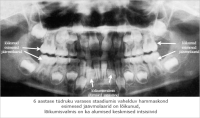

röntgenpilt

(1)

hammaste areng